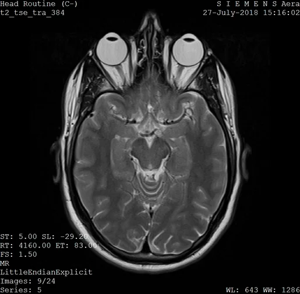

Headache and rhinorrhoea

Diagnosis: Sinusitis

Certainty: Certain

Author: Sadia Noreen

Date Published: Jan 23, 2025

Disease Specialty: ENT

Image Type:

CT Scan